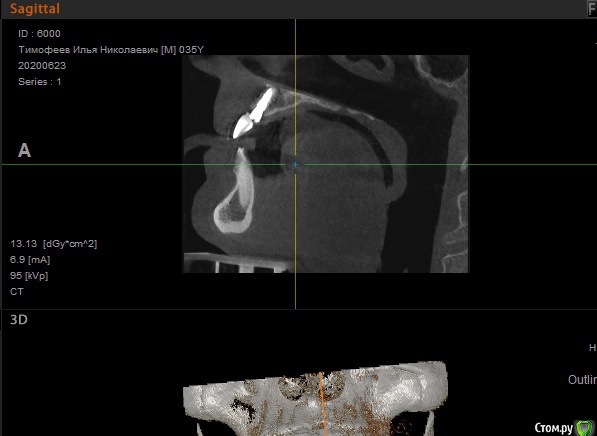

Илья Т. Опубликовано 24 июня, 2020 Поделиться Опубликовано 24 июня, 2020 (изменено) Добрый день! 3 месяца назад была проведена имплантация 21 зуба, до этого за еще за 3 месяца был удален этот зуб и в лунку заложен костный материал (т.к имплантолог изучив КТ сказал что кости не много и сверху находится пазуха, необходимо подсыпать костный материал туда). 1 июля идти с КТ на слепки, сделав вчера КТ решил посмотреть его сам и меня смутило, что в некоторых положениях справа от имплантата (где нёбо) как бы пустота? А когда подкрутив колесико на мышке как бы меняется резкость, то она пропадает? Можно ли по скринам определить нормально ли интегрировался имплантат и нормальный ли объем костной ткани? Изменено 24 июня, 2020 пользователем Илья Т. Ссылка на комментарий

Irouil Опубликовано 24 июня, 2020 Поделиться Опубликовано 24 июня, 2020 Пустота - скорее всего просто засветка от имплантата. Снимки выглядят нормально. Интеграция имплантов проверяется не по снимкам 3 Ссылка на комментарий

Илья Т. Опубликовано 2 июля, 2020 Автор Поделиться Опубликовано 2 июля, 2020 Снимки выглядят нормально.А подскажите ещё с фронтальной части достаточно объема кости? Просто где то прочитал, что чтобы имплантат долго стоял необходимо сколько то миллиметров кости вокруг него чтобы было обязательно... Ссылка на комментарий

red_butler Опубликовано 2 июля, 2020 Поделиться Опубликовано 2 июля, 2020 А подскажите ещё с фронтальной части достаточно объема кости? ДОСТАТОЧНО 1 Ссылка на комментарий